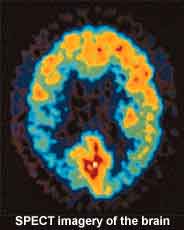

Using an advanced type of brain scan, the single-photon emission computed tomography (SPECT), they have demonstrated irregularities and reduced chemical binding in this GABA receptor in people with severe tinnitus. They hypothesize that this deficiency in the GABA receptor is directly related to the worsening of tinnitus, which is marked by increased emotional difficulty, anxiety, stress, depression and fear.

Using an advanced type of brain scan, the single-photon emission computed tomography (SPECT), they have demonstrated irregularities and reduced chemical binding in this GABA receptor in people with severe tinnitus. They hypothesize that this deficiency in the GABA receptor is directly related to the worsening of tinnitus, which is marked by increased emotional difficulty, anxiety, stress, depression and fear.

Subsequent brain SPECT studies were obtained in 10 of the 19 patients. All of them revealed improvement in the irregularities in the medial temporal lobe system.